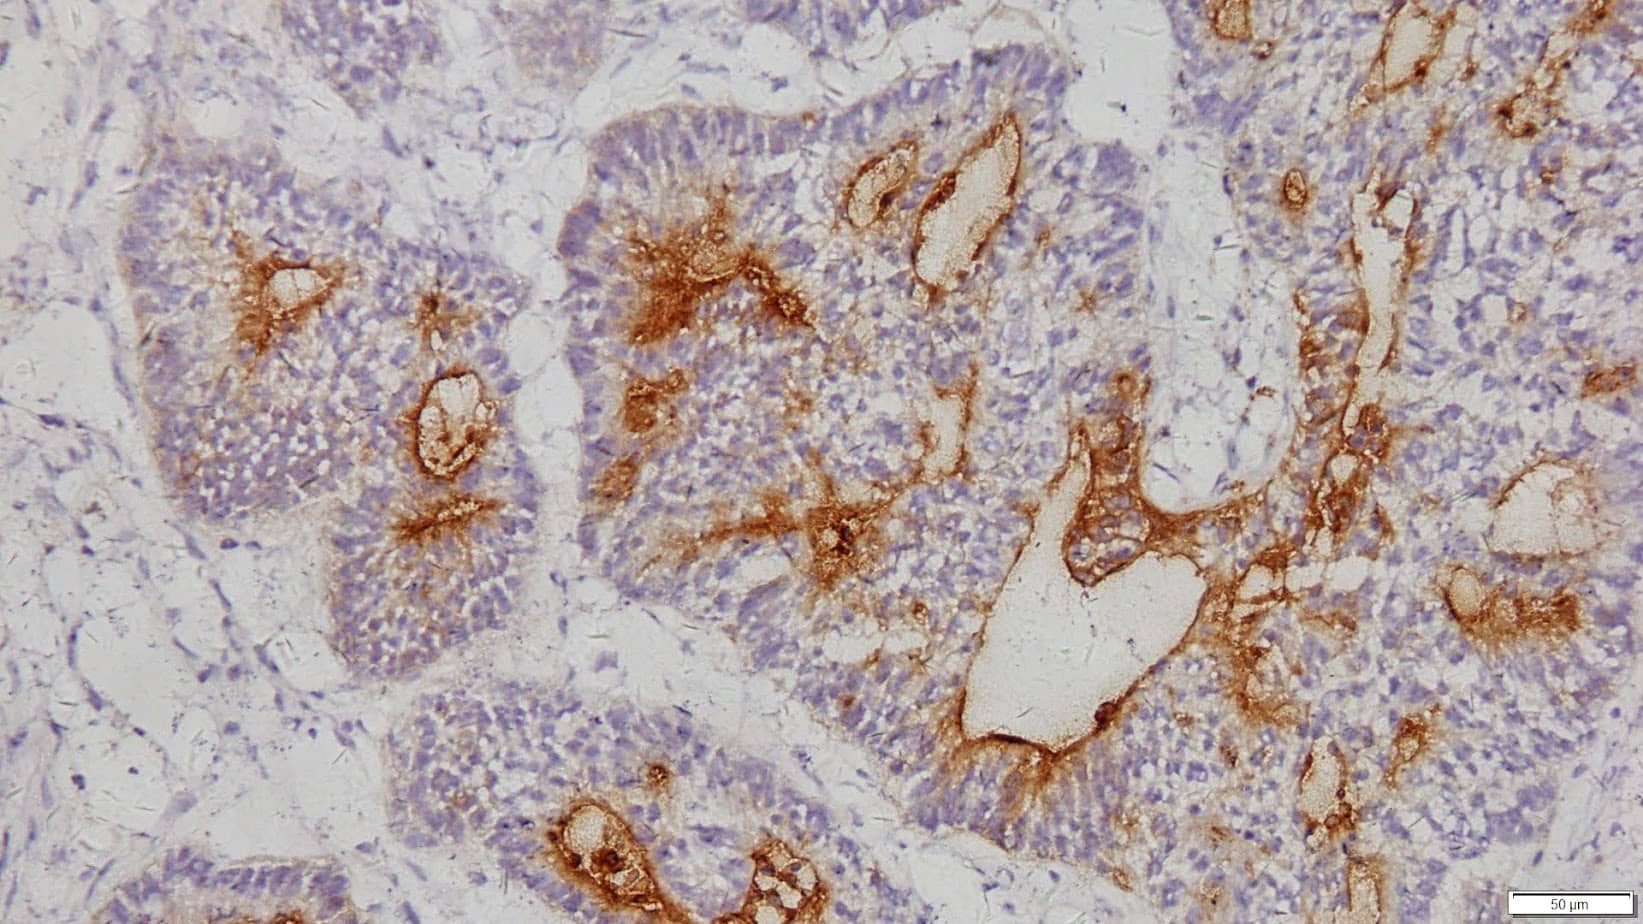

Anti-Carcino Embryonic Antigen (CEA) is a polymerized horseradish peroxidase (pHRP) labeled CEA (C135) antibody that reacts with CEA and CEA-like proteins. CEA (Anti-Carcino Embryonic Antigen), also known as CD66e, is intended for laboratory use to qualitatively identify by light microscopy the presence of CEA which is often detected in glycocalyx of fetal epithelial cells and may play a role in the metastasis of cancer cells. CEA is usually considered an epithelial marker with strong staining in adenocarcinomas. CEA has been used to distinguish adenocarcinoma (lung) vs. epithelioid mesothelioma with a 97% specific for lung adenocarcinoma, negative for mesothelioma. A high level of CEA may be suggestive of malignant breast cancer, not benign breast disease in FNA fluid.